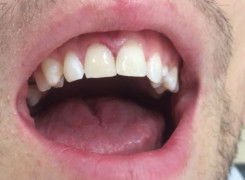

Pan Kamil zgłosił się do gabinetu po wypadku rowerowym w wyniku którego wybił ząb – lewą górną jedynkę. W takiej sytuacji została podjęta decyzja o implantacji natychmiastowej oraz zapatrzeniu pacjenta na czas integracji wszczepu w uzupełnienie tymczasowe.

Poniżej przebieg odbudowy protetycznej.